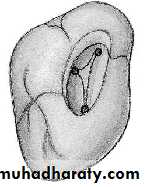

7- Mandibular 1st Molar

- There are 3 canals, 2 mesial “mesiobuccal and mesiolingual” and one locateddistally.

- We start preparation in mesial part of the tooth and access

opening is triangular-rectangular in shape.

- There is a possibility of 2 canals located distally (33%)

“and they may end with separate orifices or joined orifice so

if the distal canal is tiny and more toward the buccal side

then the possibility of 2 canals is high but if it is in the center buccolingually

then the possibility of one canal is high.